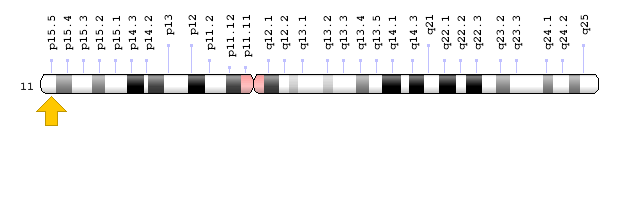

Primero hay que empezar con reparar el desequilibrio de tú ADN y la relación entre los elementos tierra y agua.

Tu ADN Tiene Un 60% de

parecido al ADN de un banano

afirmaciones que ya han sido confirmadas y divulgadas científicamente por la revista Nature.

Y hay un dato que pocos diabéticos conocen, y es el hecho que la insulina que se inyectan los diabéticos era extraída del páncreas de los cerdos.

Para que te vayas dando cuenta de que tan igual somos a los animales y que todos nos alimentamos de lo que proviene de la tierra y el agua.

Y te soy sincero, la totalidad de las enfermedades tienen un factor genético asociado…

es decir que si hay problemas en los genes ninguna solución que actúe sobre niveles físicos o biológicos va poder acabar en definitiva con el problema.

De la única forma en que la diabetes tiene solución es recomponiendo el ADN de los genes que tienes dañados

Porque si se arregla el ADN se arreglan en su mayoría todos los problemas de salud que presentas.

Antes de que haya inflamación, antes de que se produzca factor de crecimiento insulínico, o antes que se produzca la diabetes…

debe dispararse una señal del genoma humano para que esto pase.

Y es que nuestro genoma es el que controla que tengas en cabello negro, los ojos azules o que midas 1.57 cms.

Bueno te diré la respuesta en este momento, parte de mi descubrimiento se centró en el genoma humano…

Lo que quiere decir reparar desde el núcleo hasta la periferia, de dentro hacia afuera, desde lo molecular a lo fisiológico.

El ajuste principal que hice a mi descubrimiento reveló que todo se origina en un gen llamado INS…

Que produce la proteína INSULINA en

los organismos Homo Sapiens.